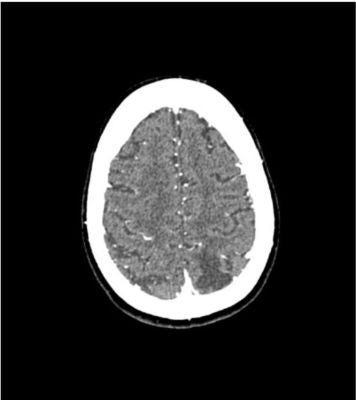

This phantom simulates a contrast medium enhanced head in arterial phase (CT angiography). It covers the vertex to the foramen magnum.

The phantom has three intracranial aneurysms of the middle cerebral artery (MCA), anterior communicating artery (ACoA), and the basilar artery.

The phantom can be used in CT (including CBCT) to evaluate and optimize imaging performance and AI-enabled diagnosis. It is also suited for training purposes.

The phantom provides a detailed and realistic simulation of common brain pathologies, soft and bone tissues. Air voids are filled with a cellulose-polymer composite of approx. -160 HU.

Diagnostic features - Aneurysms:

• Middle cerebral artery (MCA)left side

• Anterior communicating artery (ACoA)left side

• Basilar artery left side